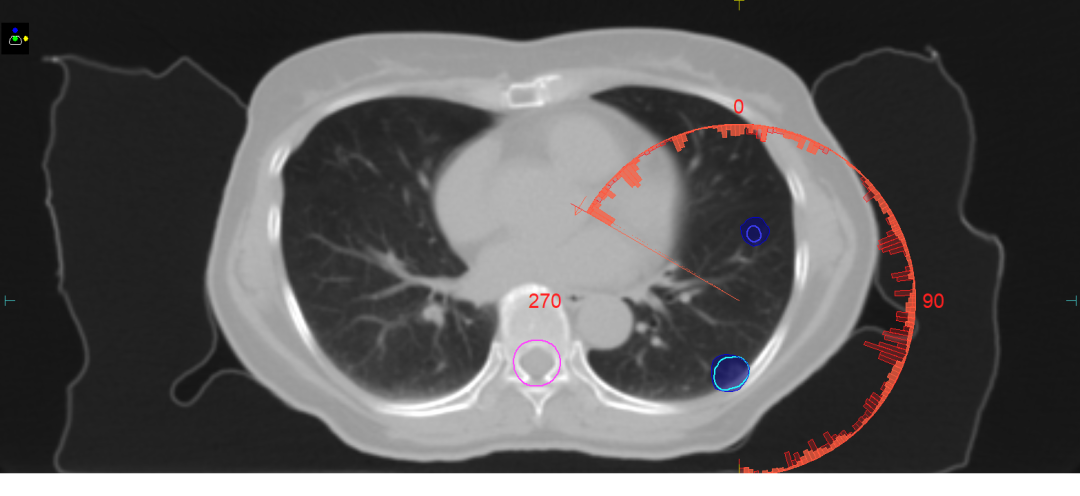

图3 运用4D CBCT定位,选择与肿瘤时间加权驻留位置图像相一致的4D CT时相画靶做计划,缩小靶区范围,降低危及器官损伤。治疗时通过分次内4D CBCT监测肿瘤位置,确保放疗精度。